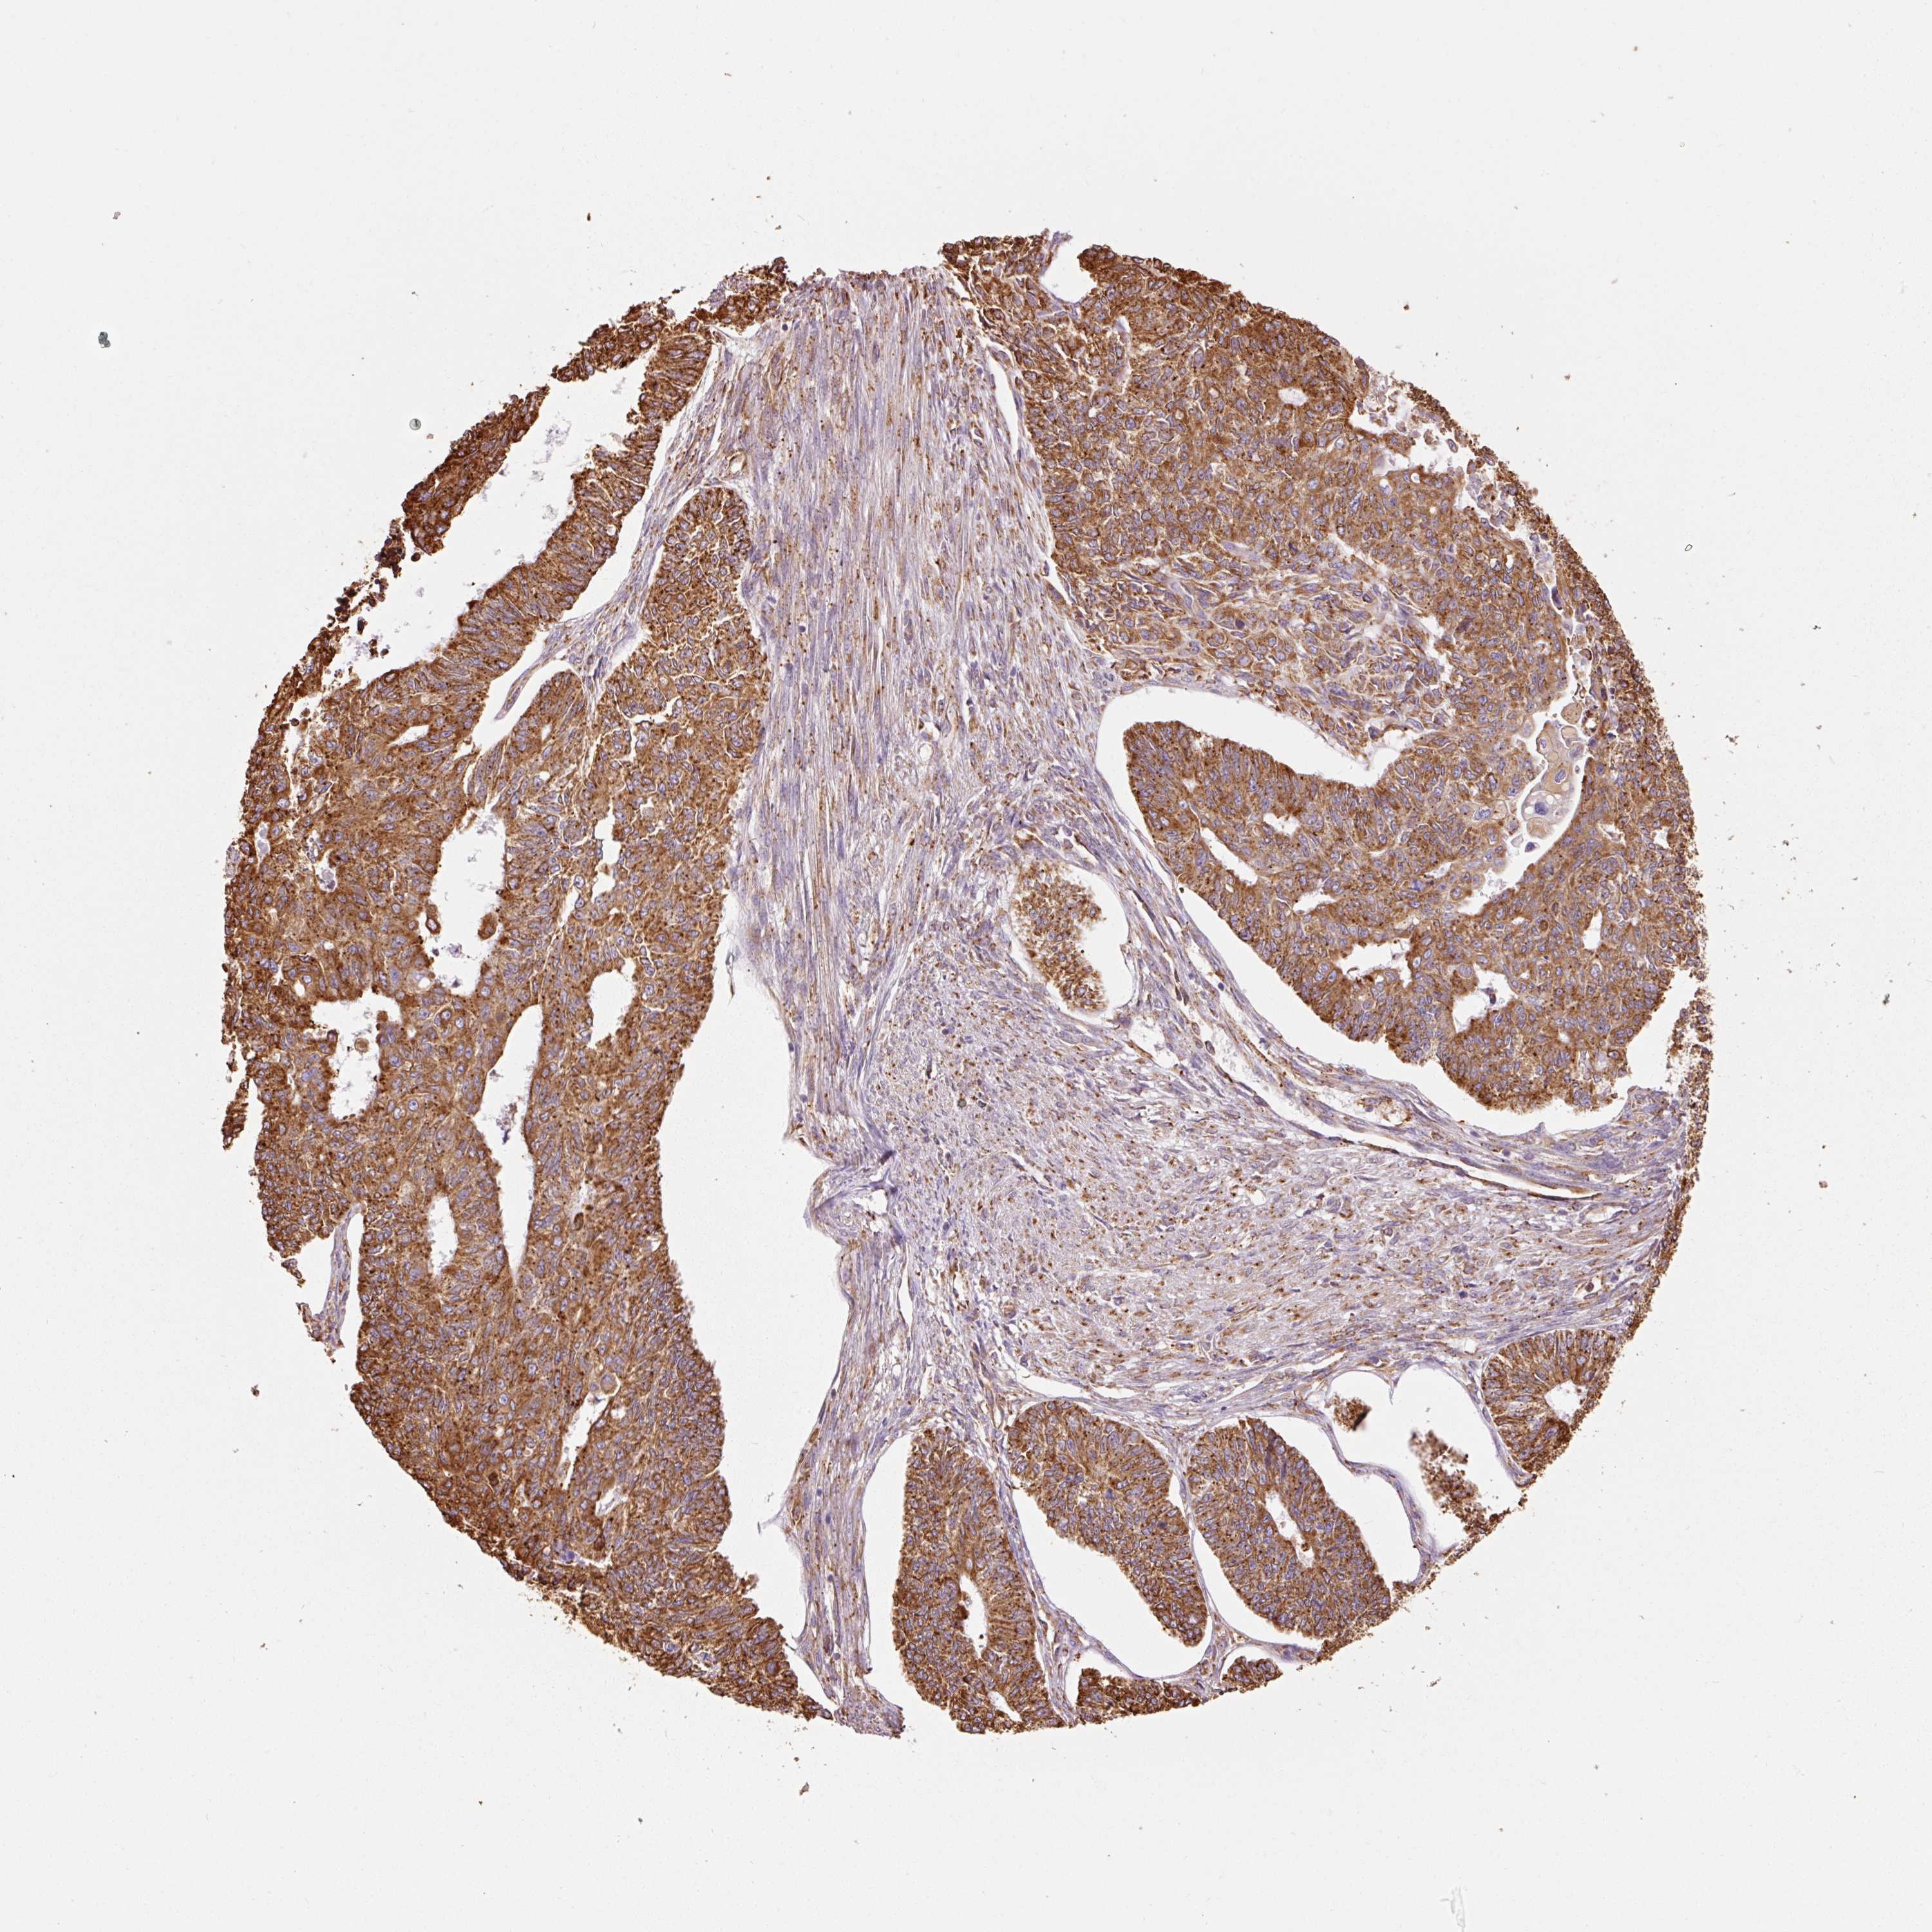

ENDOMETRIAL CANCER - Protein expressioni

A mouse-over function shows sample information and annotation data. Click on an image to view it in a full screen mode. Samples can be filtered based on level of antibody staining by selecting one or several of the following categories: high, medium, low and not detected. The assay and annotation is described here.

Note that samples used for immunohistochemistry by the Human Protein Atlas do not correspond to samples in the TCGA dataset.

Antibody stainingi

Antibody staining in the annotated cell types in the current human tissue is reported as not detected, low, medium, or high, based on conventional immunohistochemistry profiling in selected tissues. This score is based on the combination of the staining intensity and fraction of stained cells.

Each image is clickable and will lead to virtual microscopy that enables deeper exploration of all samples and also displays staining intensity scores, fraction scores and subcellular localization as well as patient and tissue information for each sample.

Antibody HPA044617

Antibody HPA052450

Staining

High

Medium

Low

Not detected

Intensity

Strong

Moderate

Weak

Negative

Quantity

>75%

75%-25%

<25%

None

Location

Nuclear

Cytoplasmic/membranous

Cytoplasmic/membranous,nuclear

Adenocarcinoma, NOS